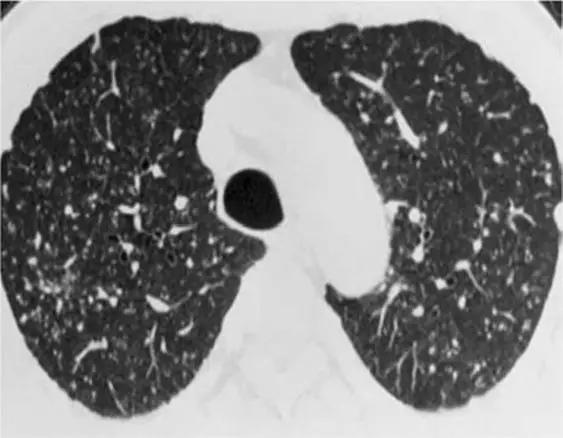

3、磨玻璃影模式

HRCT上的磨玻璃样改变被定义为不透明的薄雾影增加,并保留了支气管和血管标记。经典疾病:亚急性过敏性肺炎(HP),其特征是磨玻璃样混浊的对称斑片或弥散性双侧区域,伴有边界义不清的小叶中心型结节。有助于将亚急性HP与其他相似疾病分开的特征是,在吸气图像和气管呼气图像上,小叶区域的衰减和多血管影。磨玻璃样的最常见的鉴别疾病是呼吸性毛细支气管炎相关的间质性肺病(RB-ILD)、脱屑性间质性肺炎(DIP)和肺囊虫性肺炎。

*亚急性过敏性肺炎。 HRCT显示“磨玻璃样”改变,有少量小叶结构,没有纤维化改变

RB-ILD可表现为中度到广泛性的双侧磨玻璃影,边界不清的小叶中心型结节,支气管壁增厚。有时,在肺基部可能会出现轻微的网状结构。区分RBILD和亚急性HP的线索是RB-ILD存在上叶轻度肺气肿,HP吸烟者存在吸烟习惯的改变。

*RB-ILD 上叶水平的HRCT显示弥散的“毛玻璃样”,小叶透亮区代表伴随的小叶肺气肿。